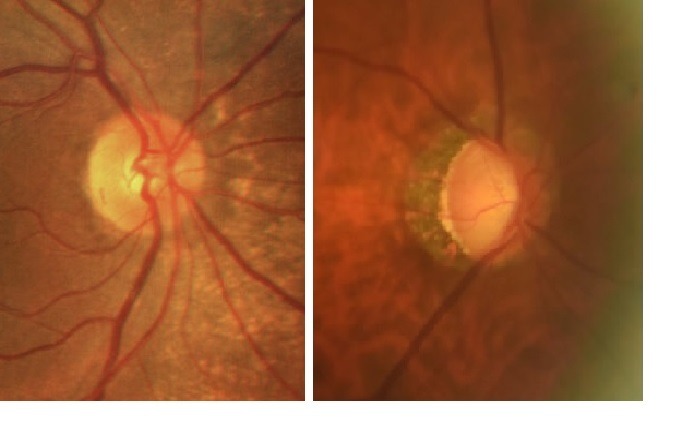

執業於台南的青光眼專科醫師林柏安提醒,絕大部分青光眼患者早期並沒有症狀,但青光眼會逐漸傷害視神經,最終導致失明。他強調,正確診斷與及早治療是預防視力受損的關鍵。

林柏安醫師指出,青光眼的高危險群包括40歲以上、家族遺傳史、高度近視或是高度遠視、糖尿病、低血壓、長期使用類固醇、眼睛有外傷等。林醫師特別強調,測量眼壓只是青光眼檢查的諸多項目之一,不能光憑「高眼壓」來診斷青光眼,尤其亞洲地區好發「正常眼壓型青光眼」,眼壓數值雖正常,卻已出現視神經傷害及視野缺損。若有疑似青光眼,需要接受眼科醫師詳細及全面的檢查。檢查建議包括以下項目:

- 眼底檢查

- 光學同調電腦斷層掃描